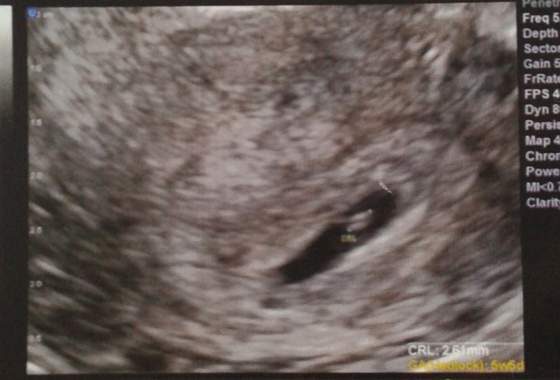

Ewel87 przyznam szczerze że jak zobaczyłam zdjęcie z usg to łzy same pociekły mi ciurkiem, gratuluję serduszka :happy:, pomimo tego całego stresu który towarzyszy ciężarówką po stracie taki widok myślę że wynagradza wszystko :tak:

Dziewczyny, przedstawiam Wam moją kruszynkę:

tętna jeszcze się nie dało zmierzyć, ale kilka razy udało się ginowi uchwycić migotanie zastawek :-):tak: kolejna wizyta 15kwietnia i jak będzie ok, to założymy kartę ciąży :-)

A krwiak się wchłonął :-):rofl2:. Na usg nic już nie było widać i gin powiedział, że te ślady na wkładce to jakieś pozostałości jeszcze mogą się wydostawać. Zmienił mi dawkowanie: ograniczamy dupka do 3 tab. dziennie a dodał 2 x luteina dowcipnie :happy: